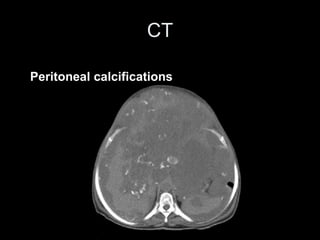

CT

Peritoneal calcifications

• the medical imaging is fundamental in the diagnosis and

the surveillance of this rare pathology. US permits a

better characterization of the ascites whereas the CT

visualizes the calcifications and the scalloping effect.